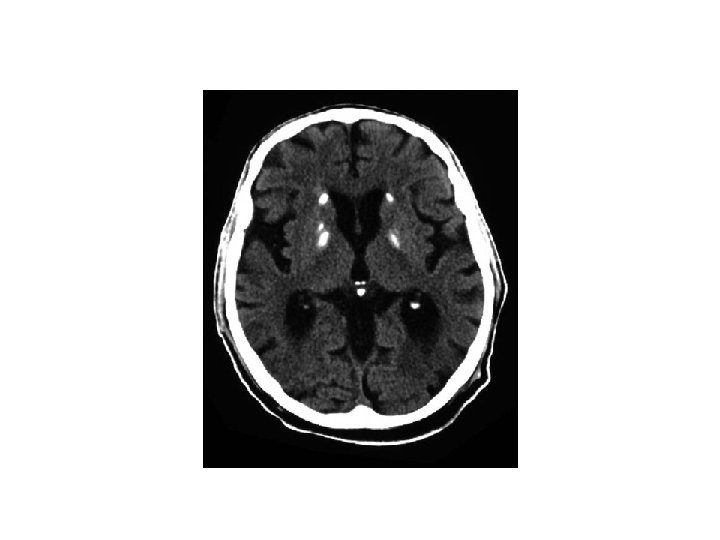

Dementia Investigations: Aimed at detecting treatable causes: FBC/U&E Blood glucose; TFTs; LFTs B 12/folate levels Lipid profile (Syphillis/HIV serology) Consider MSU/CXR +/- CT head